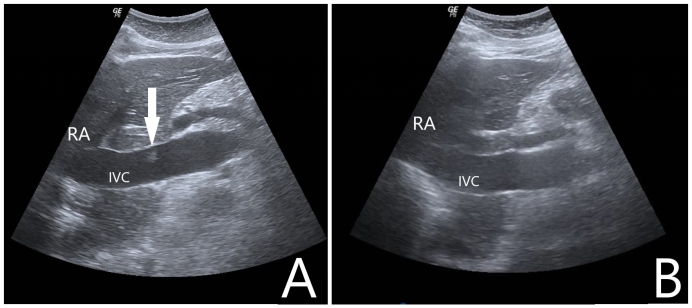

1 一般资料病例1:女性,68岁,农民,既往有“高血压病”“扩张型心肌病”“左束支传导阻滞”史,未规律诊治。主诉“突发意识不清1.5 h”于2021-02-07入院。入急诊时心搏呼吸未闻及,予高级生命支持,心电监护提示室颤,除颤治疗无效,征得家属同意后行机械按压下ECMO支持。超声引导下V-A模式上机,ECMO参数设定:转速3 500 r/min,流速3.3 L/min,吸入氧浓度(FiO2) 100%,气流量3 L/min。ECMO成功转机后停止胸外按压,患者出现ROSC,复查床旁心电图提示“右束支传导阻滞”。患者转运至介入室行经皮冠脉造影提示左右冠主干及各支未见病变,行头颅CT、胸腹主动脉CTA检查未见明显异常,考虑本次系扩张型心肌病合并双侧束支传导阻滞引起心搏骤停,予安置临时起搏器。ECMO上机后共使用肝素3 000 U,返回急诊ICU后给予全身肝素化抗凝,每2 h监测一次活化部分促凝血酶原激酶时间(activated partial thromboplastin time,APTT),目标APTT维持在60~80 s。入院后第1天患者出现消化道出血、穿刺处大量渗血、ECMO流量不稳定,血常规提示血红蛋白进行性下降,心脏彩超检查提示左室腔55 mm,左心室射血分数(left ventricular ejection fraction,LVEF):21%,左室壁运动普遍弥漫性减弱,给予输红细胞悬液6 U、新鲜冰冻血浆2 900 mL并调整肝素抗凝强度使得APTT维持在50~60 s。入院后第3天患者消化道出血及穿刺处渗血好转,停血管活性药物,未再发恶性心律失常。入院后第4天撤除ECMO,撤机前ECMO参数设定:转速2 250 r/min,流速1.8 L/min,吸入氧浓度40%,气流量3 L/min。入院后第5天心脏彩超提示LVEF:39%,同时发现下腔静脉距离右心房入口4 cm左右有附壁血栓形成,长约1.09 cm,宽0.5 cm,随血流飘动(如图 1A所示),筛查下肢其他部位未见明显血栓形成,遂给予依诺肝素钠100 IU/kg皮下注射每12 h一次治疗。入院后第7天行超声检查下腔静脉未见明显异常回声(如图 1B所示),考虑抗凝治疗后血栓消失。住院期间患者未出现过下腔静脉综合征或肺栓塞的症状或体征。经过后期的心肺康复治疗患者于2021-03-11出院,意识水平恢复正常,遗留双下肢肌力下降。

| A:箭头显示超声下在下腔静脉处附壁漂浮的血栓;B:经治疗后超声在下腔静脉未见明显异常回声;RA:右心房,IVC:下腔静脉 图 1 撤离ECMO 1 d后行下腔静脉超声检查 |